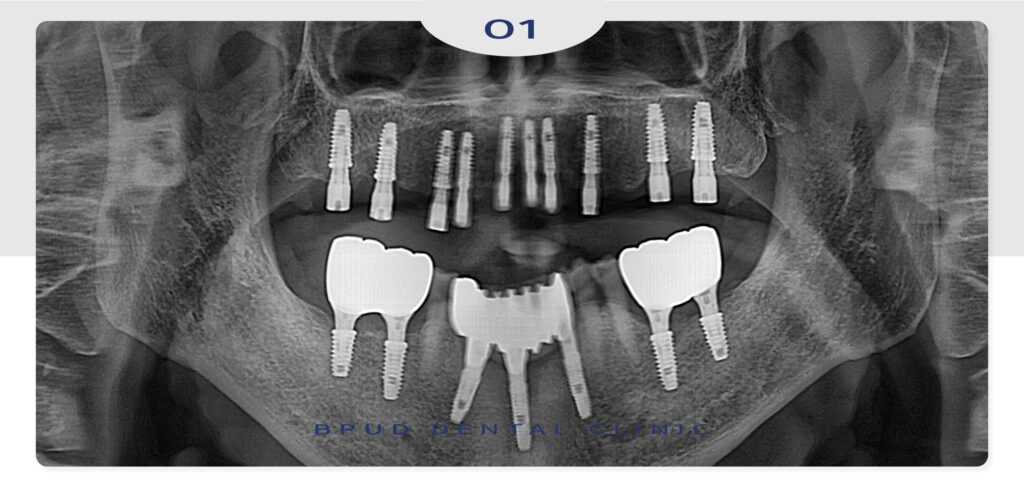

24.03.30

오늘은 오랫동안 방치해두었던 치아들을

치료하기 위해 부평치과를 내원해 주신

환자분을 소개해 드려보려고 합니다.

이미 부평치과에서 아래쪽 앞니의 임플란트

식립을 진행하셨지만 오랜 기간 내원하지 않으시다가

왼쪽 위 치아들의 통증이 느껴지신다고 하셨는데요.

남아 있는 치아들 모두 심한 충치와 염증으로 인해

살려쓰기에는 힘들어 모두 발치 후 10개의 임플란트를

식립하여 전체를 수복하기로 하였고

아래쪽도 양쪽 어금니 부위에 두개씩 임플란트를

식립하여 총 4개를 수복하도록 계획을 수립하였습니다.